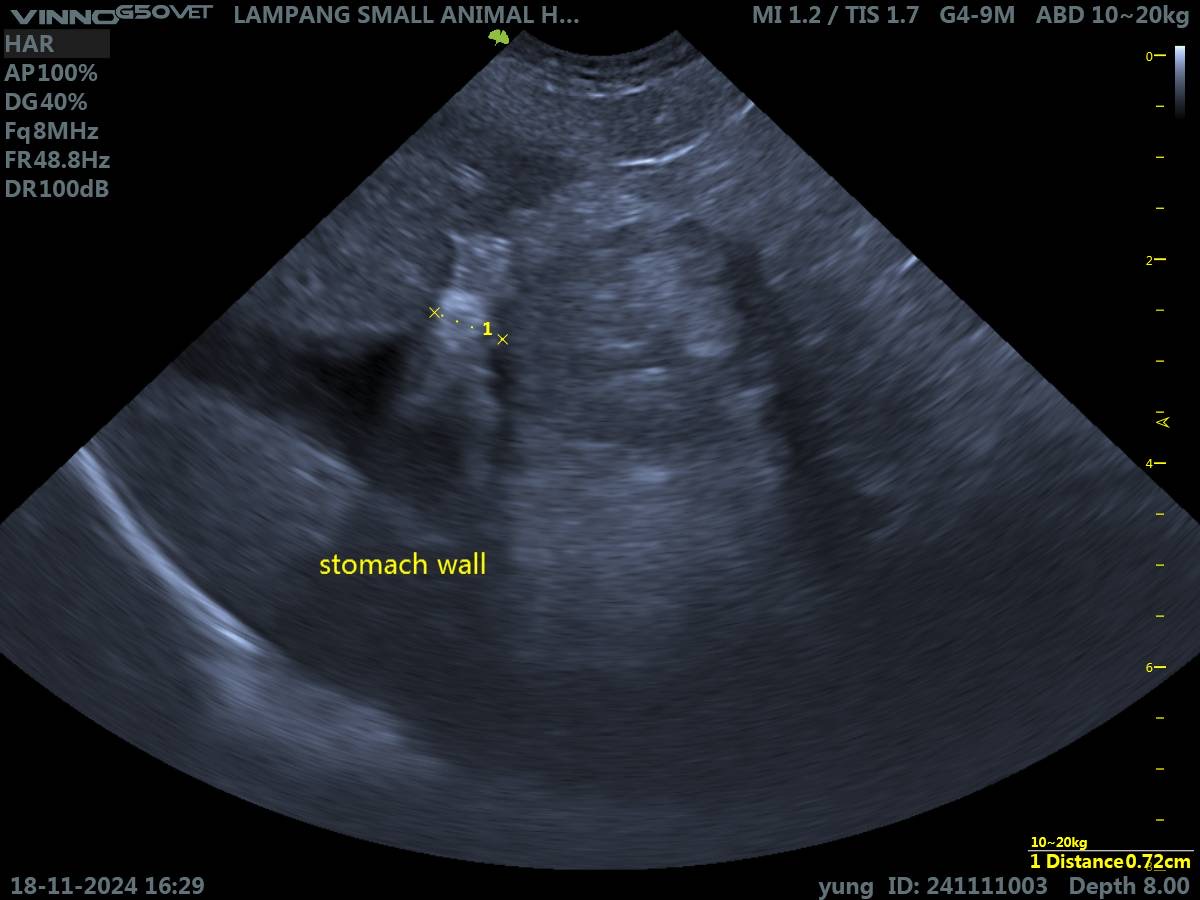

ลักษณะของอาหารที่อาเจียนออกมายังเป็นรูปทรงอยู่ เหมือนน่าจะยังไม่ได้ย่อยค่ะ กินข้าวสัก 10-15 นาทีอาเจียนออกมาแล้ว แต่กินอาหารได้ปกตินะคะ ส่วนการขับถ่ายเนื่องจากเลี้ยงระบบปล่อยเลยไม่เห็นน้องขับถ่ายเลยค่ะเพราะมักจะไปทำธุระกันข้างนอก น้องเคยกินยาจำพวก ลดอาเจียน, ลดกรดในกระเพาะ, เคลือบกระเพาะ มาแล้ว แต่ก็ยังไม่ดีขึ้นค่ะ เคยไปเอกซเรย์คุณหมอบอกไม่มีปัญหาอะไร ส่วนอัลตราซาวด์คร่าว ๆ ว่ามีแผลในกระเพาะอาหารจนเห็นเป็นพังผืดในกระเพาะค่ะ ทำได้แต่ให้ยาไปเรื่อย ๆ แต่ก็ยังไม่ดีขึ้นค่ะ น้องกินยาไปแล้วอ้วกออกมากับอาหารบ้างก็มี เดี๋ยวนี้ช่วงนอนน้องจะครางหนักมากด้วยค่ะ ขออนุญาตส่งผลอัลตราซาวด์ให้ผู้มีความรู้ด้านนี้พิจารณาหน่อยนะคะ ว่าสามารถมีแนวทางการรักษาได้อย่างไรบ้าง ผ่าตัดได้ไหม หรือฉีดยาอะไรได้บ้างไหม ขอบคุณค่ะ🙇🏻♀️ เพื่อน ๆ คนอื่นก็สามารถแสดงความคิดเห็นได้เลยค่ะ เผื่อน้องหมามีอาการคล้าย ๆ กันจะได้มาแชร์กันค่ะ🥹